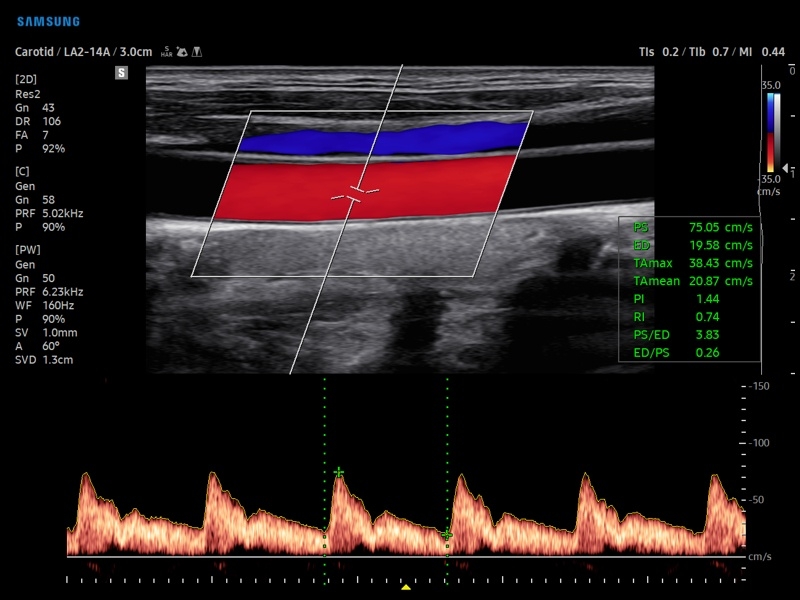

• Модуль AutoIMT - автоматическое вычисление комплекса интима-медиа общей сонной артерии (Intima Media Thickness). Данная оценка имеет большое значение для ранней диагностики атеросклероза и оценки риска развития инсульта и инфаркта миокарда.

• Модуль 2D Arterial Analysis программа, позволяющая автоматически провести анализ толщины и эластичности стенок разных участков сонной артерии, с выведением результатов в графической форме в движении (кинопетле) аналогично программе Strain для эхокардиографии.

• Сонные артерии:автоматическая, полуавтоматическая, ручная трассировка доплеровского спектра; ПСС, КДС, %СтПлощ, %Ст Диам, площадь сосуда, диаметр сосуда, средняя толщина интимы, объемный кровоток.

• Расширенная сосудистая визуализация: Auto IMT+, 2D Arterial Analysis